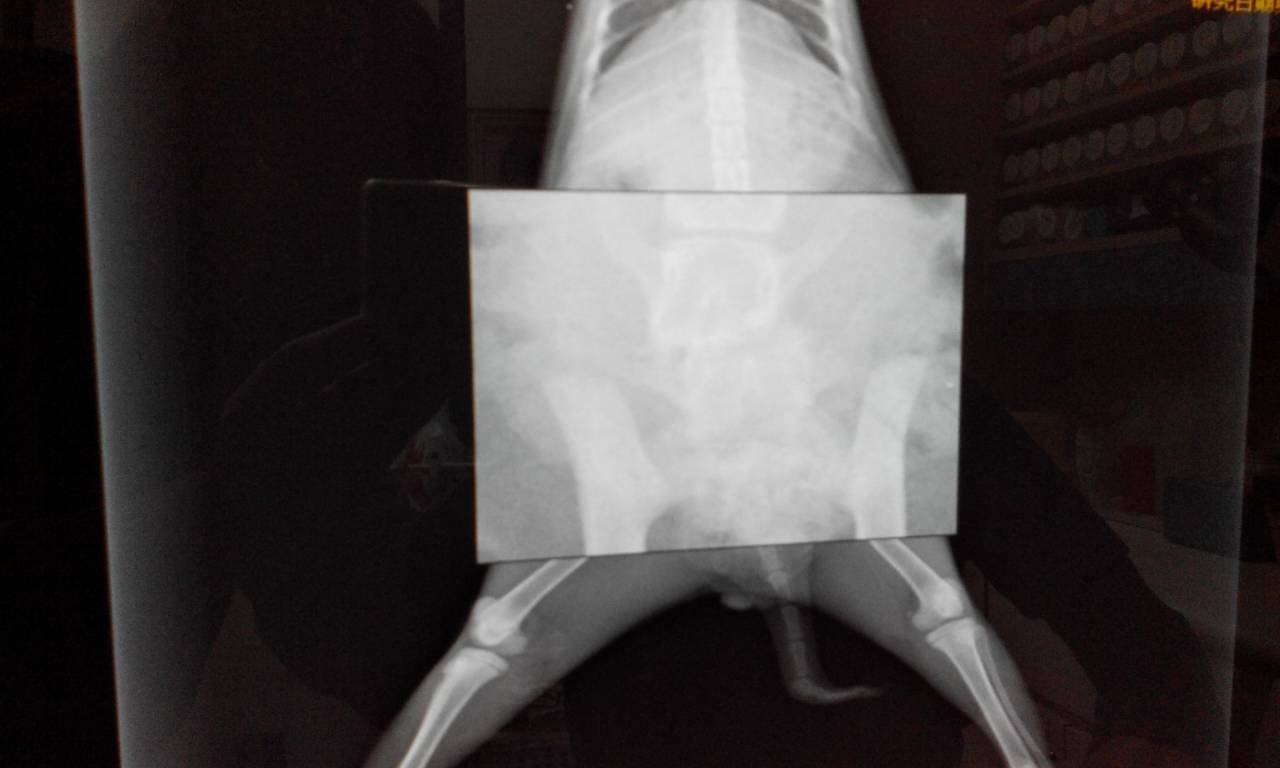

- 編號: 5675

主題: 被獵犬追殺的小冰 申請者姓名: 鄭紫淳 花色: 申請日期: 2015-04-08 21:27:45 申請者部落格: 申請者臉書網址: 所在縣市/合作醫院: 高雄市/新德民動物醫院 治療費用: 16560元 需求人數: 19人 已結案 (2021-06-03 00:05:55) 報名人員: Chihchia Chang x2(已付款)、Patrick、lenneth(已付款)、黃素芬(已付款)、memin、CC(已付款)、mandy lin(已付款)、Egg Sh(已付款)、Shan Chou x10(已付款)、PhoebeWang(已付款)、ERic YU(已付款)、 候補人員: 陳筱惠、李坤財、 動物病情說明: 半夜五點,小冰在我家門口被四隻獵犬追殺,像五馬分屍那般咬著不放,我斥喝牠們,小冰卻受了重傷,後腿用拖的拖到車底下,好不容易她拖到我身邊 動物近況說明: 傷口恢復的不錯,仍需要擠尿擠便,左後腳小腿骨頭有問題,所以無法正常行走